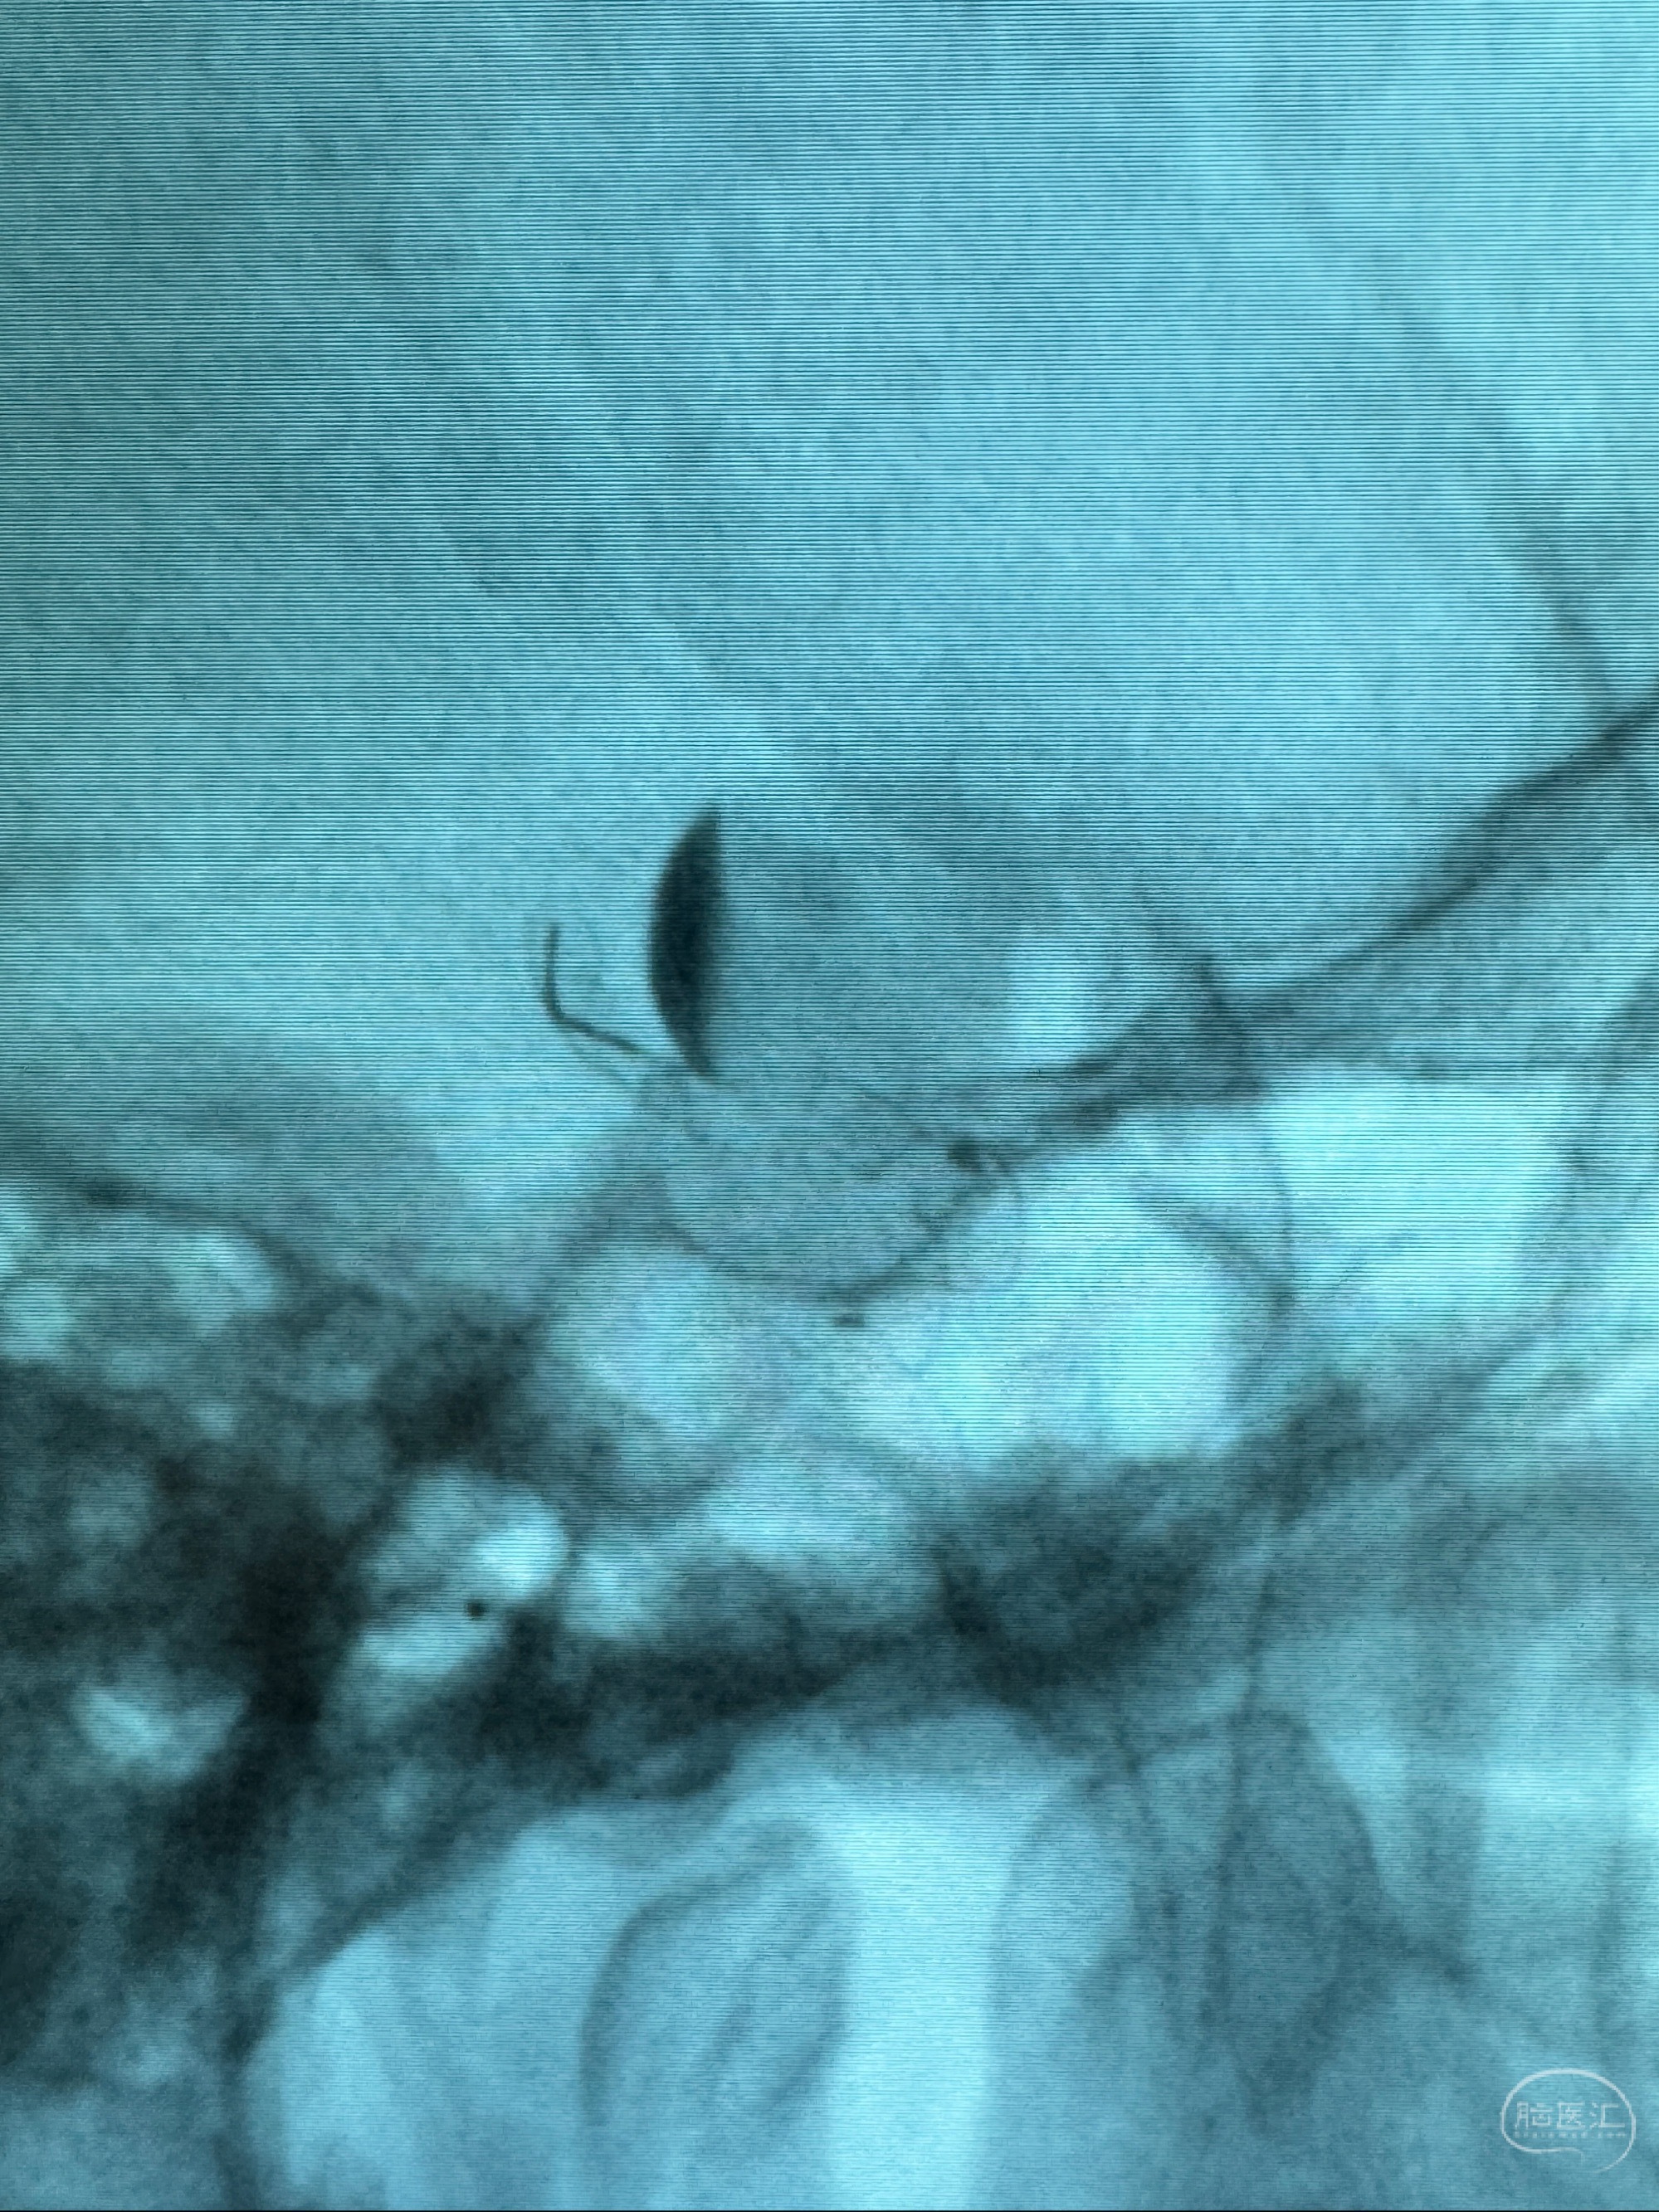

透视可见红圈部分为支架导管的头端

手推冒烟显示支架位置及展开情况,箭头为支架导管的位置

尝试回收支架失败,只能考虑释放支架了

逐帧图像展示歪着脖子释放支架,旁边吩咐助手手机摄影、拍照留像(透视机不能留影像)